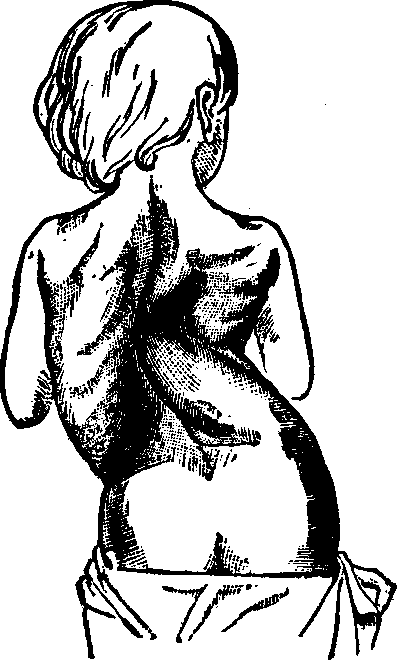

Fig.

24. A representation of the superficial layer of muscles on the anterior

portion of the body.

Fig.

25. A representation of the superficial layer of muscles on the posterior

portion of the body.